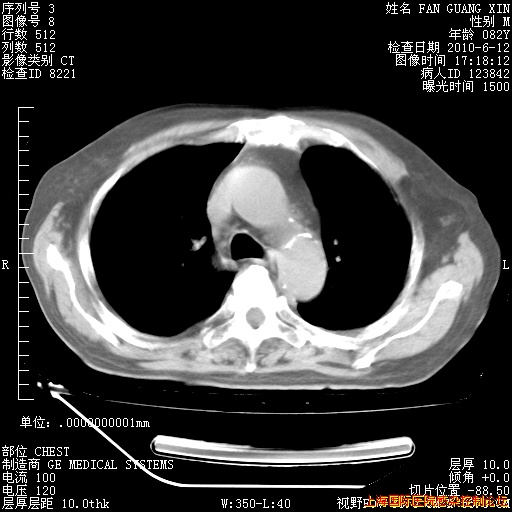

6月12日纵膈窗

回复